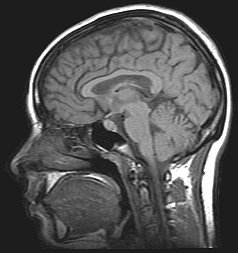

What creates a genius? Is it simply a function of having the right brain patterns, or is there a deeper mechanism at work? Just as savants like Daniel Tammet and Alonso Clemons demonstrate superhuman mastery in certain subjects, there have been people throughout history who gained extraordinary abilities from freak accidents. Unfortunately, genius often comes at a price.

Somehow, his brain injury had given him the ability to, well, see math. When researchers imaged Padgett’s brain and showed him a series of equations, the visual processing centers in his brain lit up. His brain was turning the numbers into pictures. Jason Padgett has since enrolled in college to learn more about his condition and the number theory behind his inexplicable visions.

Researchers are still struggling to understand the mechanisms behind the miraculous few who have acquired unexpected abilities from debilitating brain damage, but their lack of knowledge is not from lack of trying. The phenomenon has been recognized for decades, and it doesn’t always lead to happiness.